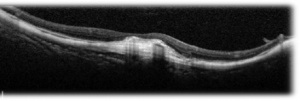

SD-OCT – Hyper-reflective lesions with fuzzy borders at the RPE, central ellipsoid, and external limiting membrane are seen on SD-OCT imaging. Generally, type 2 CNVM are seen in the pathological myopia cases. Subretinal hemorrhage, intraretinal fluid , subretinal fluid or RPE detachment may also be seen. Enhanced depth imaging (EDI) enables visualization of choroid layers as well which typically demonstrates atrophy in myopic eyes without CNVM and fibrosis or thickening in myopic eyes with CNVM present

SS-OCT – Swept source imaging is particularly useful for diagnosis and follow-up of myopic CNVM. Chorioretinal thinning along with subretinal membrane may be seen in SS-OCT in eyes with myopic CNVM (Fig 2, 3). Better delineation of choroid layers is also possible with SS-OCT.